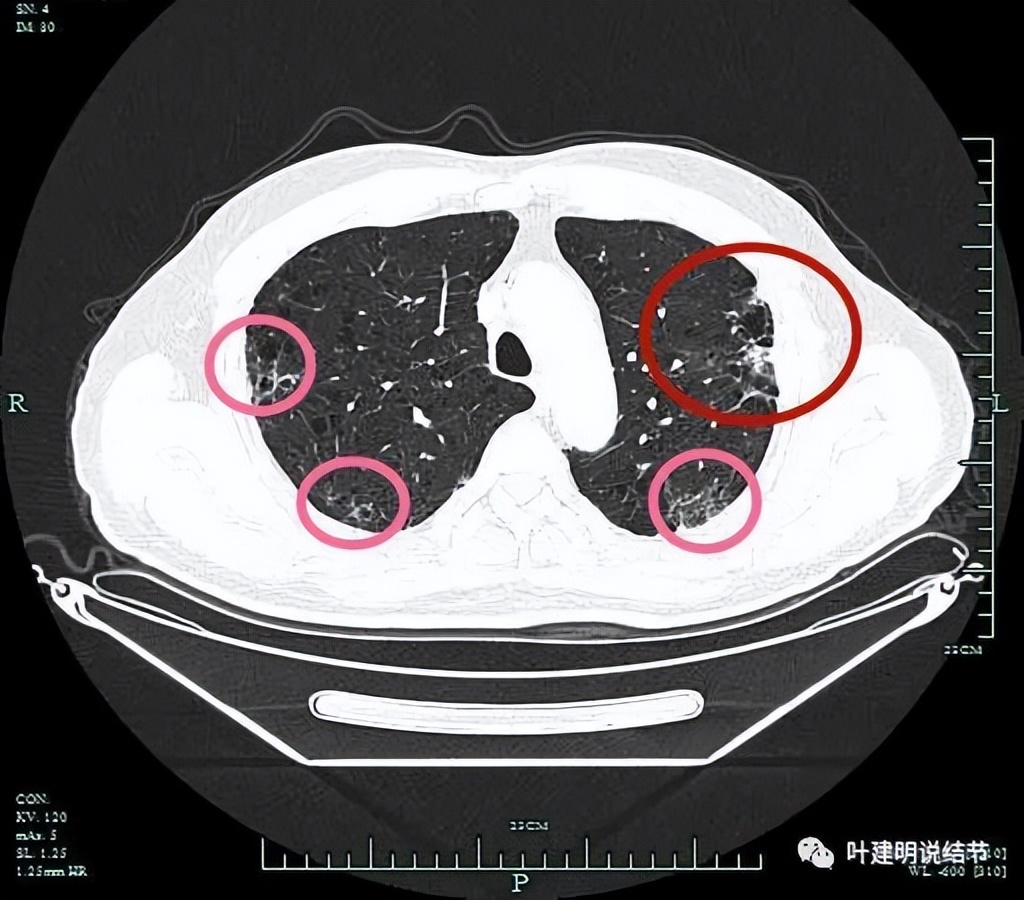

左上病灶开始出现,周围伴慢性炎的表现(红色圈起来部位);其他余部分有多处炎性改变(粉色圈起来的)。